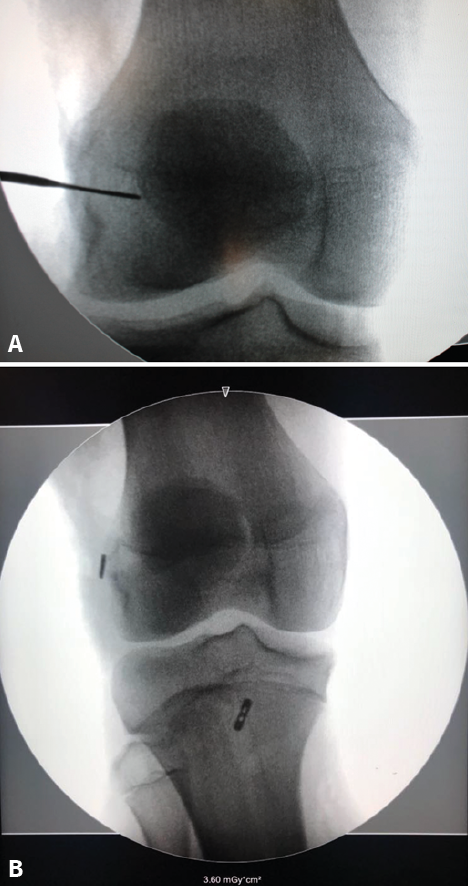

Figure 6. Intraoperative radioscopic view of a reconstruction of the anterior cruciate ligament (ACL) in a skeletally immature patient with the partial transphyseal technique. A: the entry point of the femoral tunnel distal to the physis is marked by a metal tip; B: postoperative control of the partial transphyseal technique, showing the cortical button of the femur in the distal femoral epiphysis and the tibial button located distal to the physis, in a more central location, to perform a more vertical tunnel and reduce physeal damage.